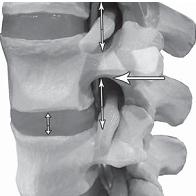

На фото № 10 макета позвоночника наблюдается нормальное взаимоотношение суставных поверхностей дугоотростчатых суставов, в норме высота межпозвонкового диска и межпозвонковых отверстий.

На фото № 11 макета позвоночника наблюдается смещение (подвывих) суставных поверхностей дугоотростчатых суставов. Подобное смещение, как правило, происходит вследствие развития дегенеративно-дистрофических процессов в межпозвонковом диске. При этом уменьшается высота диска, сужается просвет фораминального отверстия (межпозвонкового), что может способствовать ущемлению спинномозговых корешков (нервов) и сосудов.

На фото № 12 макета позвоночника наблюдается перерастяжение дугоотростчатого сустава вследствие вытяжения, расширение фораминального отверстия, а также растяжение задних отделов фиброзного кольца межпозвонкового диска и сближение вентральных (передних) отделов тел позвонков. Это приводит межпозвонковый диск в клиновидное состояние, что способствует выталкиванию содержимого межпозвонкового диска из передних его отделов в задние.